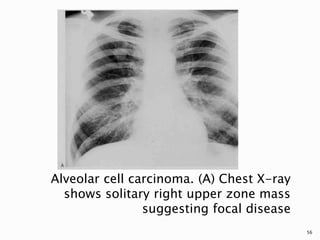

 Lung cancer occasionally takes the form of

focal or multifocal consolidation, typically

with bronchioalveolar carcinoma (BAC).

 Although the most common appearance of

BAC is as a SPN (43%), consolidation is the

second most common radiographic pattern

(30%).

52

53

 This pattern is caused by tumour growth

along the framework of peripheral airways

and alveoli, combined with mucoid

secretions.

 Air bronchograms and air alveolograms are

characteristic, but not specific, features.

54

 A pattern of focal or multifocal nodularity can

result from involvement of one or more acini,

and when confluent, can resemble non-

neoplastic conditions, such as pneumonia,

aspiration, or edema.

 The consolidative pattern has a poorer

prognosis than the solitary nodular pattern.

Alveolar cell carcinoma. (A) Chest X-ray

shows solitary right upper zone mass

suggesting focal disease